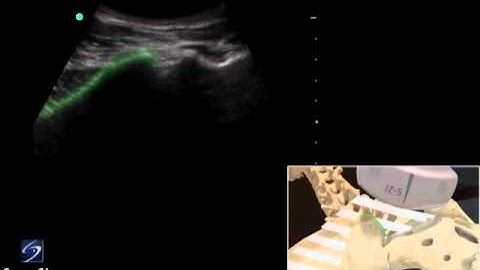

Ultrasound guided facet joint injections